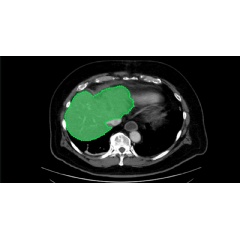

AI Assisted Spleen Segmentation

The startup offers active learning for data labeling across multiple industries. For healthcare data labeling, its platform integrates with the NVIDIA Clara Deploy SDK, allowing customers to use the software toolkit for AI-assisted segmentation of healthcare datasets.